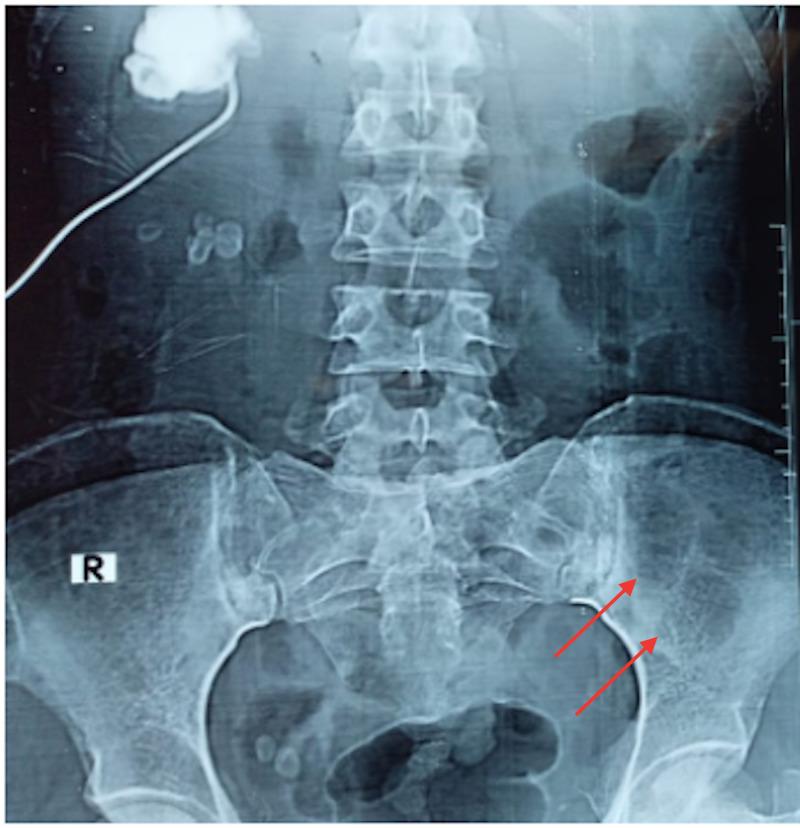

Multiple myeloma (MM), a common hematologic malignancy, is predominantly a disease of old age with a median age at diagnosis hovering around 70 years. Medical literature remains largely bereft of reports of the ailment in young female patients. We chronicle the case of a 26-year-old female patient who presented with a history of fever, weight loss, constipation, frequent infections, and back and chest pain. Laboratory workup divulged underlying anemia, renal impairment, increased calcium, and significant urinary proteins, insinuating a diagnosis of MM. Subsequent bone marrow examination confirmed a diagnosis of MM. Following treatment with a concoction of dexamethasone, cyclophosphamide and bortezomib, the patient improved rapidly, and her clinical symptoms abated. This article further accentuates the need for physicians to be cognizant of the possibility of early-onset MM in unusually young patients.

多发性骨髓瘤(MM)是一种常见的血液系统恶性肿瘤,主要是一种老年疾病,诊断时的中位年龄徘徊在70岁左右。医学文献中关于年轻女性患者患此病的报道仍然很少。我们记录了一名26岁女性患者的病例,她有发热、体重减轻、便秘、频繁感染以及背部和胸部疼痛的病史。实验室检查发现有潜在的贫血、肾功能损害、血钙升高和大量尿蛋白,提示诊断为MM。随后的骨髓检查确诊为MM。在用地塞米松、环磷酰胺和硼替佐米联合治疗后,患者迅速好转,临床症状减轻。本文进一步强调了医生需要认识到异常年轻患者中早发性MM的可能性。